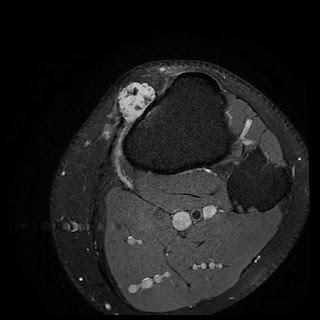

Tibial plateau fracture (Schatzker VI) | Radiology Case ...

Tibial plateau fracture (Schatzker VI) | Radiology Case ... from images.radiopaedia.org